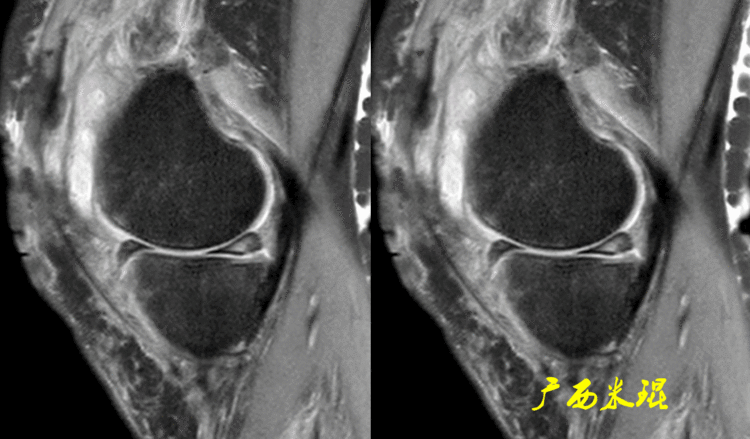

2、从发病机制诊断半月板损伤并不是每个病人都能够这么清晰的显示半月板的信号改变,同样这张MR,我们发现患者出现明显的对吻征,対吻征是诊断ACL损伤的重要体征,说明病人受伤的同时膝关节扭转严重,甚至出现轴移,这种情况下(损伤/发病机制)外侧半月板后根极其容易受伤,我们再认真的阅看其他截面,就很容易找到半月板损伤的佐证。